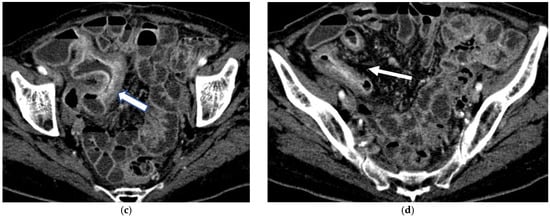

Figure 4.

(a,b) Axial CT scan in the venous phase after administration of positive oral contrast medium (Gastrografin) showing thickened terminal ileum in a 65-year-old patient with Crohn’s disease. (c,d) Coronal CT scan in the venous phase after administration of positive oral contrast medium (Gastrografin) showing thickened terminal ileum (arrows) in a 65-year-old patient with Crohn’s disease.

Figure 5.

(a,b) Coronal CT scan in the venous phase after administration of negative oral contrast medium (PEG-solution) showing thickened ileal loops (arrows) in an 85-year-old female patient with Crohn’s disease. (c,d) axial CT scan in the venous phase after administration of negative oral contrast medium (PEG-solution) showing thickened ileal loop (arrows) in an 85-year-old female patient with Crohn’s disease.